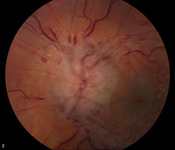

Idiopathic intracranial hypertension

Bilateral disc oedema

From the personal collection of Dr M. Wall; used with permission